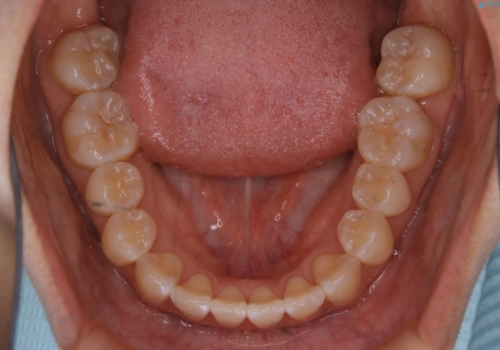

前歯のがたつきとオープンバイト:インビザラインでまとめて治す

- 噛み合わせと、前歯のがたつきが気になるとご相談にいらした方です。インビザラインFULLで綺麗な歯並びと噛み合わせを作ることが出来ました。

オープンバイトの方への治療は、通常抜歯を行いワイヤーによる矯正治療を行うことが多いですが、今回はインビザラインの特性を生かし、非抜歯にて綺麗な歯並びを作ることが出来ました。

舌癖がある方は、歯を内側から押し出す力が日常的に働くため、矯正治療後も歯と歯の隙間が開いてしまうなどの後戻りのリスクが高いことが知られています。舌の正しいポジショニングやお口周りの筋肉のトレーニングを行うことで後戻りのリスクを減らすことが可能です。